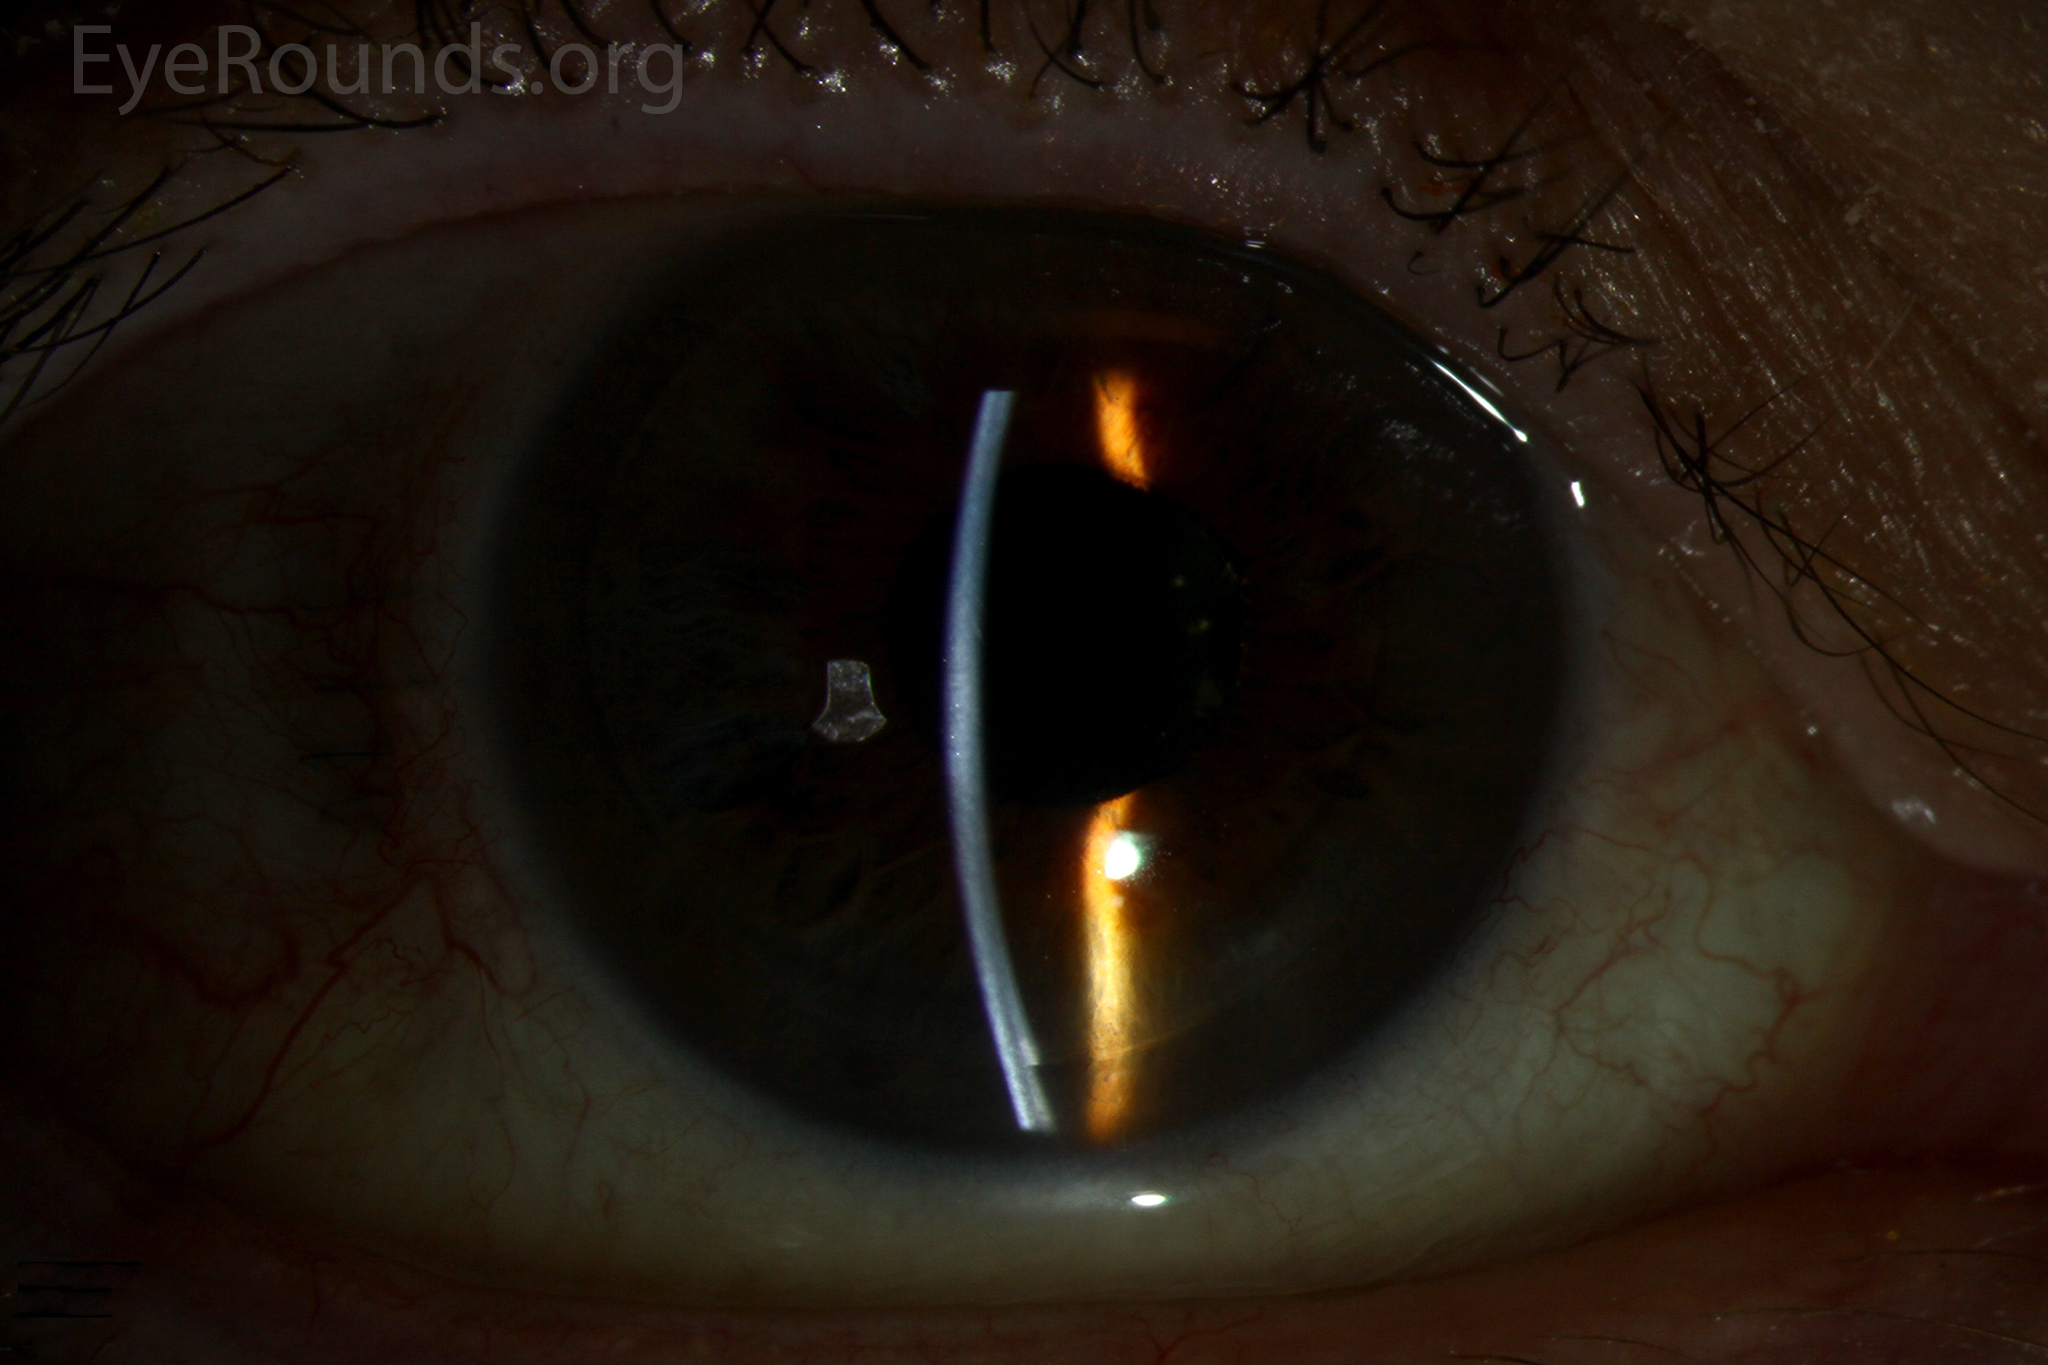

PK is a full-thickness transplant procedure, in which a trephine of an appropriate diameter is used to make a full-thickness resection of the patient's cornea, followed by placement of a full-thickness donor corneal graft. Interrupted and/or running sutures are placed in radial fashion at equal tension to minimize post-operative astigmatism (Figure 2). Later, the sutures are removed selectively to reduce the amount of astigmatism present. A transplant can last decades with proper care (Figure 3). While once the most prominent type of corneal transplant, PK has been supplanted by partial thickness techniques for endothelial dysfunction without significant stromal scarring. PKs are performed primarily for visually significant stromal scarring, opacities with an uncertain status of the endothelium or significant posterior corneal involvement, corneal ectasia (such as keratoconus and pellucid marginal degeneration, especially if there is history of hydrops), combined stromal and epithelial disease (such as Peters anomaly), and infectious or non-infectious corneal ulcerations or perforations (1, 14). A variant of the procedure, the mini-PK, can be used to treat more focal defects in the cornea (Figure 4).